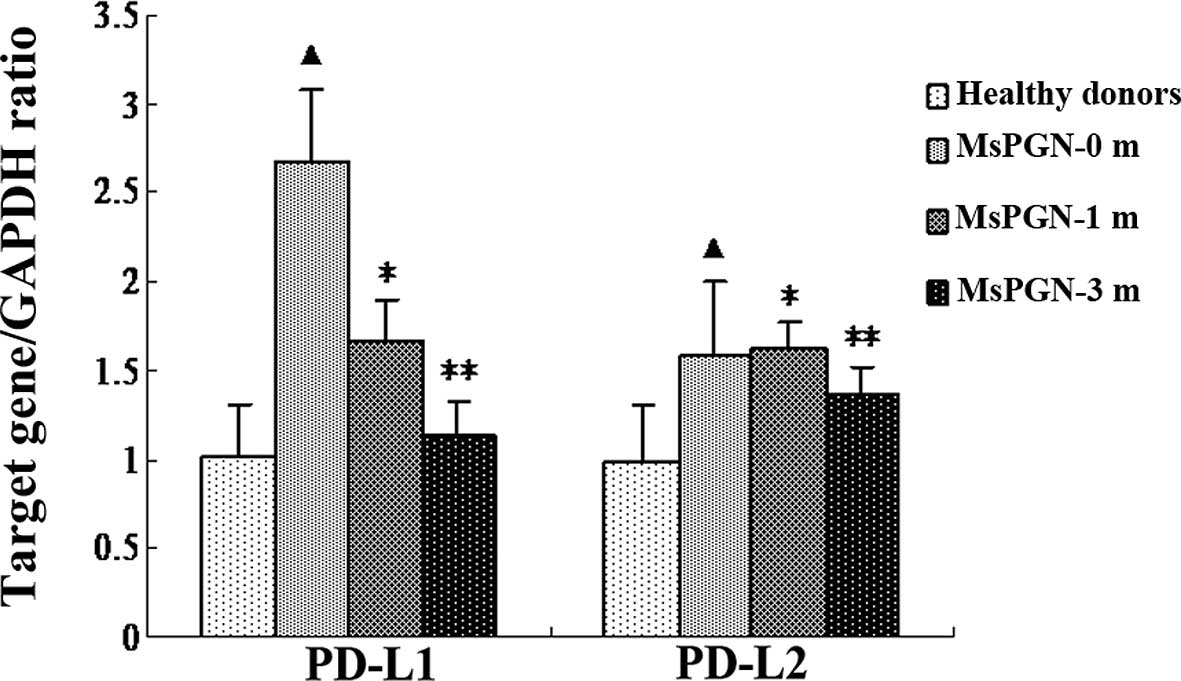

Quantitative real-time RT-PCR was used to measure

the expression levels of the PD-L1 and PD-L2 mRNA in the PBMCs from

the 10 healthy donors and 25 patients with MsPGN, at 0, 1 and 3

months subsequent to initiation of treatment with sinomenine. As

shown in Fig. 2, the PBMCs from

the MsPGN patients expressed high levels of the PD-L1 (P=0.037)

mRNA compared with the controls. There were no significant

differences in the expression of PD-L2 mRNA between the MsPGN

patients and the controls (P=0.627). The expression of the PD-L1

mRNA was suppressed by sinomenine. The decrease in the PD-L1

expression was detected at 1 (P=0.034) and 3 months (P=0.002).

However, sinomenine did not affect the expression of the PD-L2 mRNA

(P=1.000).